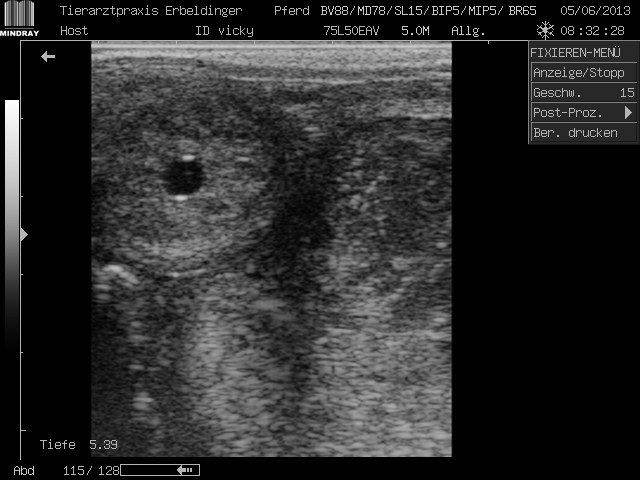

Ultraschall

Je nach Größe des Tieres stehen uns verschiedene Ultraschallgeräte zur Verfügung. Wir sind in der Großtierbehandlung spezialisiert auf gynäkololgische Untersuchungen. Hier bieten wir deutschlandweit vor allem die Untersuchungen auf Trächtigkeit bei Equiden unter 1 m an. Hierzu kann sich jeder zu unserer Deutschlandtour im Herbst anmelden. Einfach email an info@avarella.de und anmelden.

Selbstverständlich bieten wir aber auch Ultraschall für Kleintiere an.

Pferd ab 14 Tag